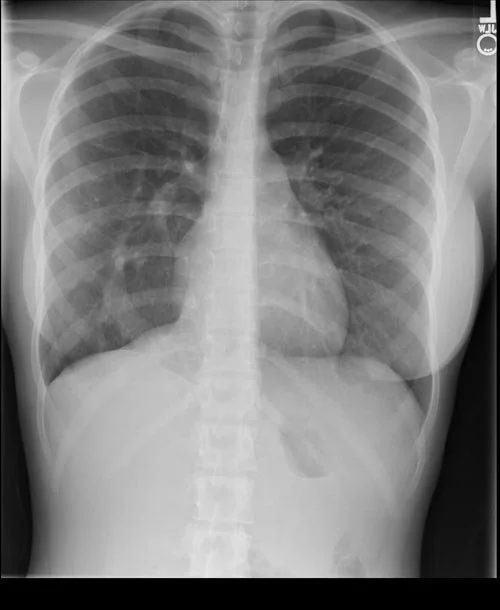

• On XR look for the scimitar - aka thick vessel looking structure on the right side

• Case courtesy of The Radswiki, Radiopaedia.org, rID: 11917 (Scimitar)